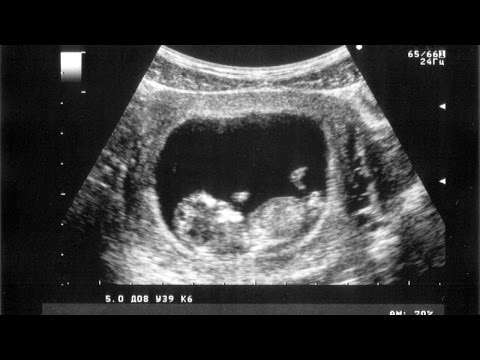

Now, their unborn son was diagnosed with hydrops, which creates excess fluid in the chest. In their child's case, the fluid was beginning to fill his lungs.

Though a bit of fluid is alright, doctors confirmed a deadly amount was accumulating, prompting surgeons at UC Davis Children's Hospital to make a bold decision.

Dr. Shinjiro Hirose followed the example set in other hospitals, such as Guangdong General by performing emergency surgery on the unborn baby while he was still in the womb.

UC Davis' first in-utero surgery occurred in September when Dr. Hirose made a small incision in Khae's abdomen and used a small catheter to drain the fluid.